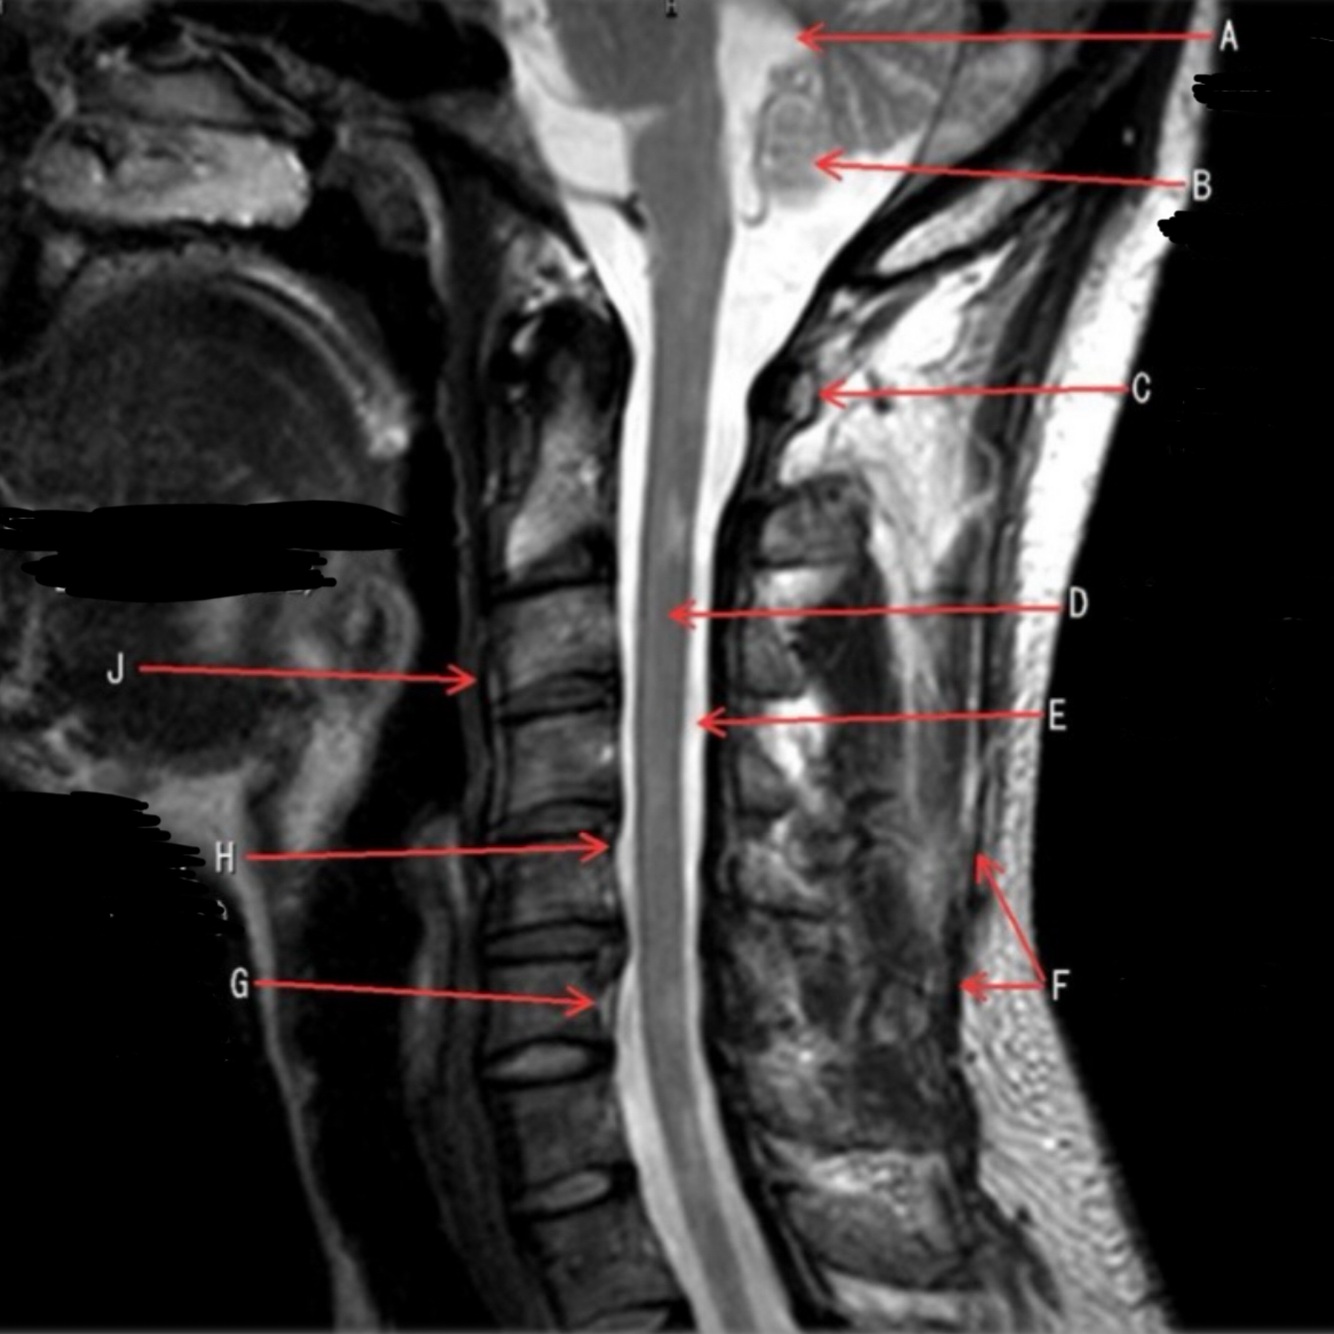

1

Q

What is letter A?

A

4TH VENTRICLE

What is letter B?

CEREBELLUM

3

What is letter C?

POSTERIOR ARCH OF C1

4

What is letter D?

6

What is letter F?

SPINOUS LIGAMENT

7

What is letter G?

VENUS PLEXUS

8

What is letter H?

POSTERIOR LONGITUDINAL LIGAMENT (PLL)

9

What is letter J?

ANTERIOR LONGITUDINAL LIGAMENT (ALL)